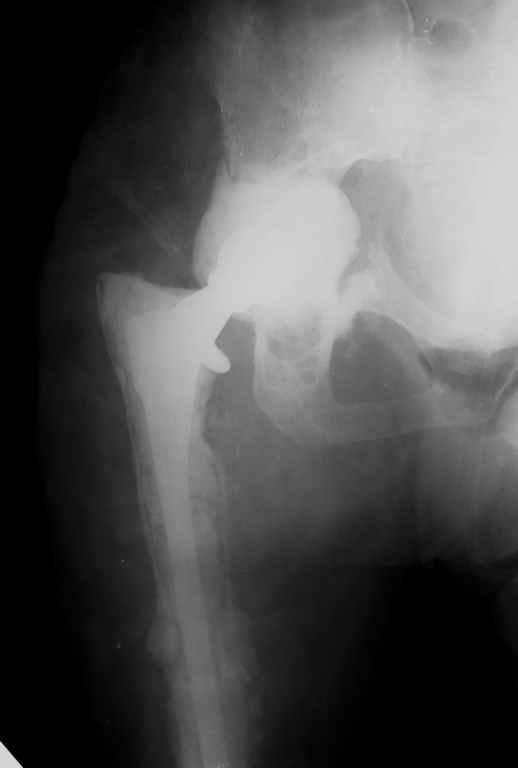

Апрель 2005 |  Декабрь 2005 |  Декабрь 2005 | Реревизия по поводу нестабильности вертлужногокомпонента была выполнена в апреле 2005 г. с пересадкой вертлужной впадины (аллотрансплантат)и защитой трансплантата кольцом Б-Ш.Нагноение выявлено через 6 месяцев, был полностью удален эндопротез (и вертлужный и бедренный компоненты), тщательная ХО мягких тканей с установкой подготовленной из цемента с антибиотиками (родной гентамицин + насыпной ванкомицин) вертлужной впадины опять же на цемент. Установлена новая ножка взамен удаленной на к/цемет с антибиотиками. Рана зажила, б-ая выписана домой. По этой методике прооперировано четверо б-х, пока без рецидива инфекции, одна из пациенток уже поступила для второго этапа.С уважением, Р.Тихилов

Большое спасибо за снимок, теперь все видно! Кстати, по этому поводу: в зоне бедренной кости кортикала осталось очень мало. Планируете ли Вы при окончательной имплантации менять эту ножку на другую (и если да, то на какую именно)?

Мы установили временный протез предназначенный только для движений и ходьбы без нагрузки. "Старый" цемент мы не удаляли поэтому спустя 3-4 месяца планируется выполнить расширенную остеотомию бедра с удалением всего к/цемента и установкой ножки бесцементной фиксации. Обязательным условием является хорошая дистальная фиксация на протяжении минимум 6-8 см. Скорее всего мы используем изогнутую ножку длиной 254 мм, это будет либо ZMR, либо Solution, я еще не планировал этот этап операции.